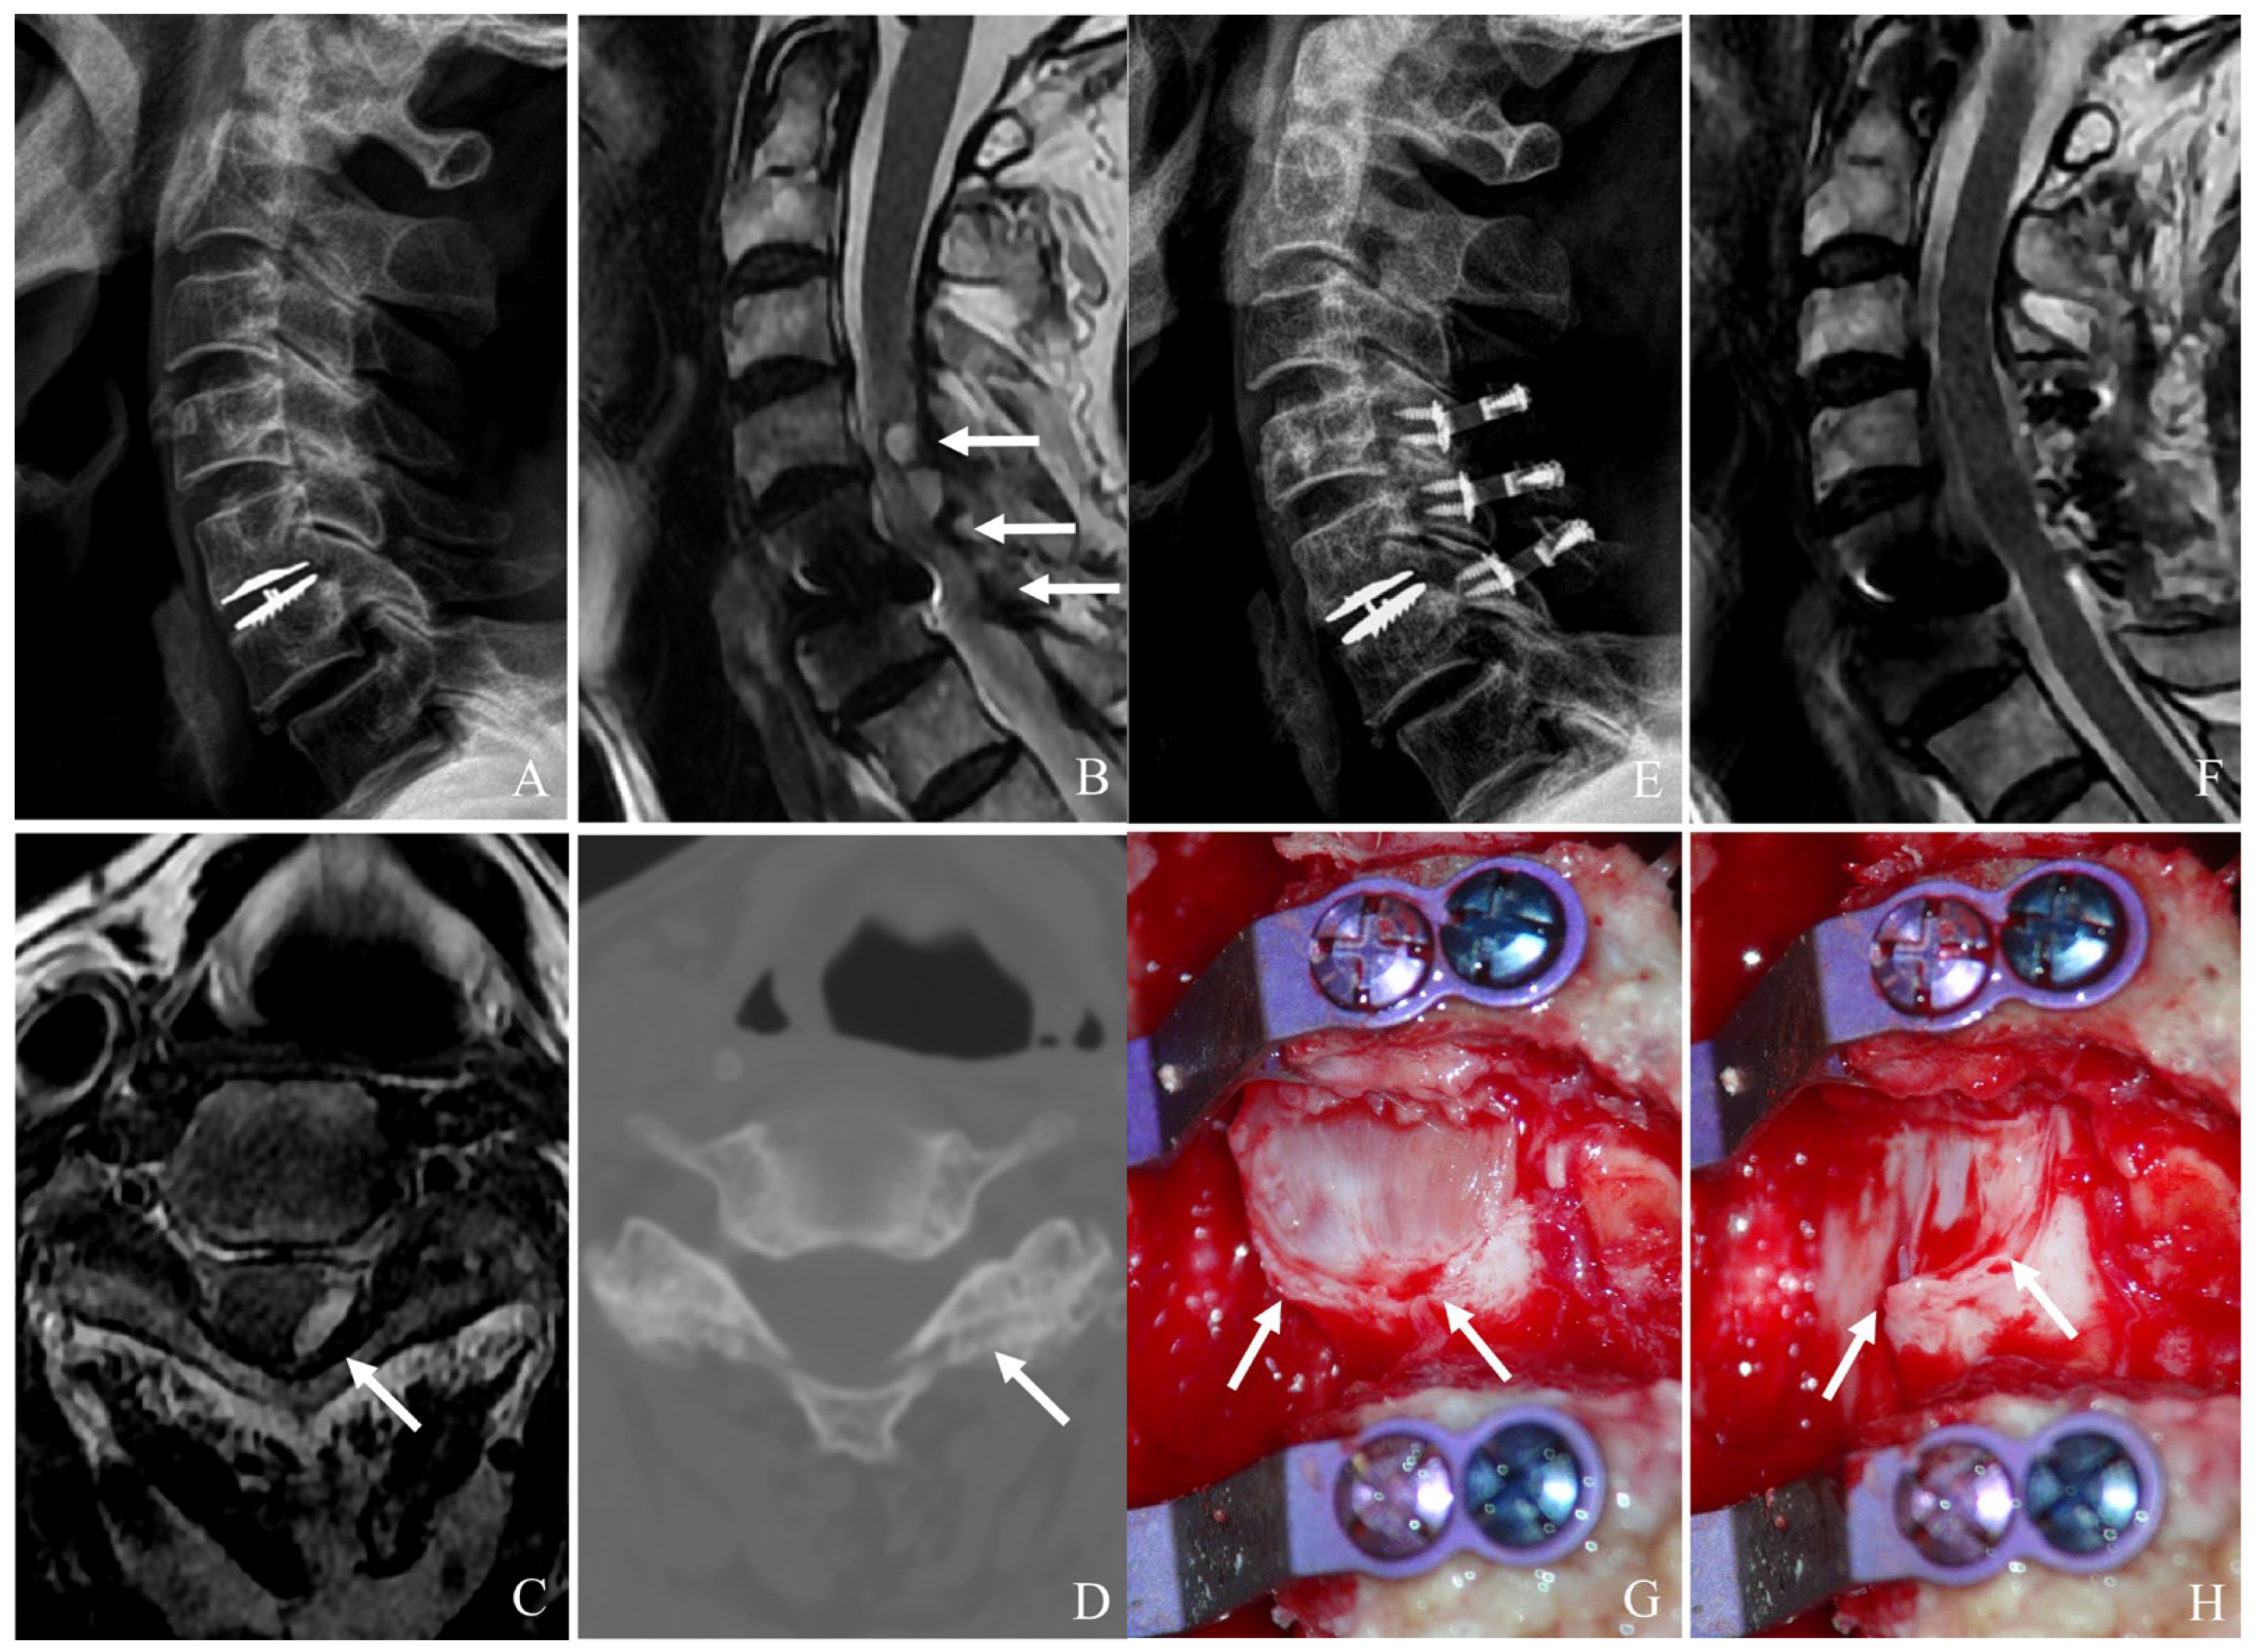

For ACDF, after device removal, the intervertebral space is prepared for fusion. A structural graft (autograft, allograft, or synthetic cage) is placed, followed by anterior plating to provide immediate stability. In cases of severe bone loss or multilevel involvement, a corpectomy may be required, with the placement of a cage or graft to restore anterior column support for ACCF (Figure 2). The decision between two-level ACCF and three-level ACDF must be individualized based on the patient’s pathology, bone quality, and sagittal alignment needs. While corpectomy provides better deformity correction, it carries higher surgical risk and requires more extensive stabilization. In contrast, three-level ACDF is less invasive but has higher rates of pseudarthrosis, potentially leading to revision surgery. Understanding these nuances allows for more tailored surgical planning and improved patient outcomes [31,32].

Figure 2. Plain X-rays (A), computed tomography (B), and magnetic resonance image (C) showing cervical disc arthroplasty at C5–6 and ossification of the posterior longitudinal ligament (OPLL) of C6 body (white arrow) causing cord compression. The patient underwent removal of the C5–6 prosthesis and OPLL and anterior cervical corpectomy and fusion (D).